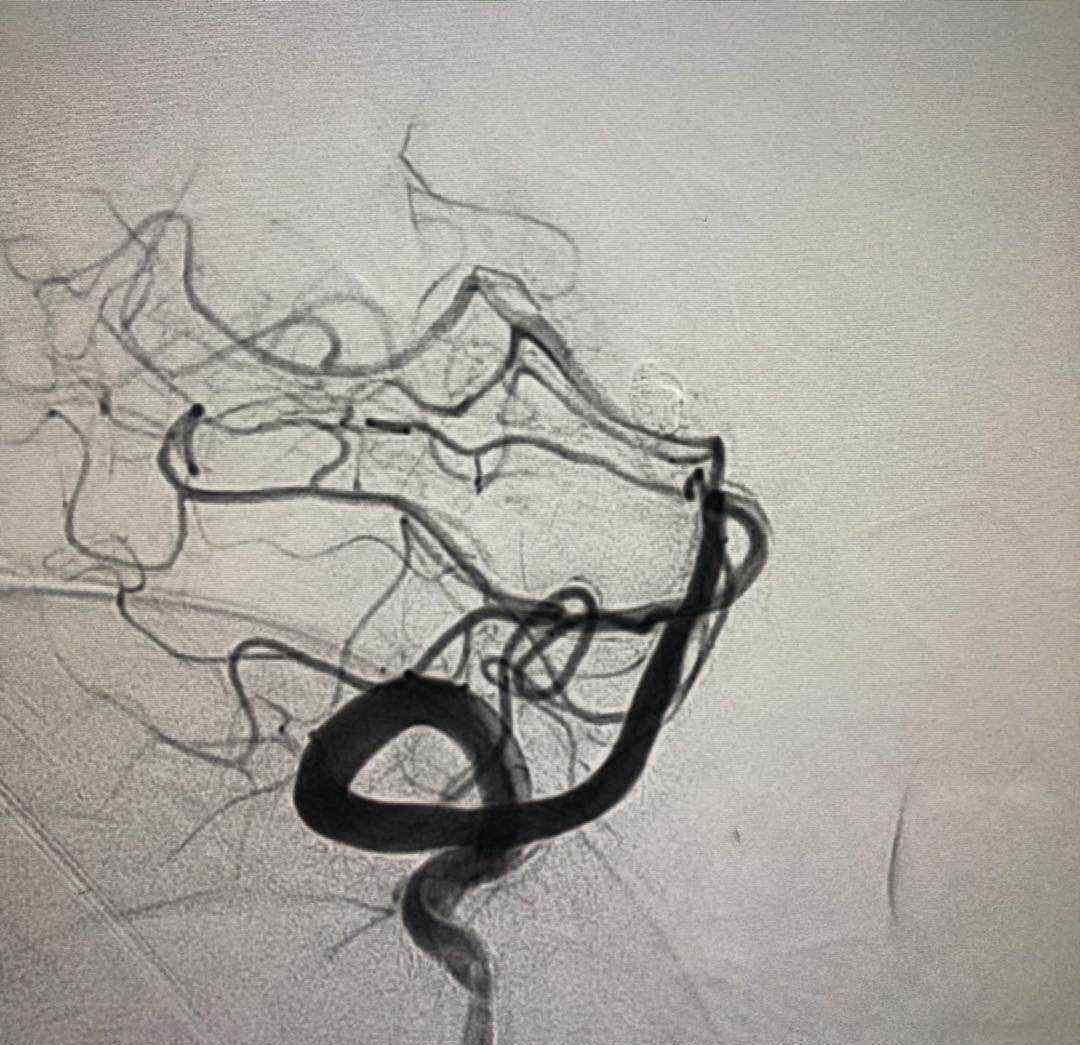

于2019.4.18日行颅内动脉瘤栓塞术

术后患者神清语明,四肢无瘫